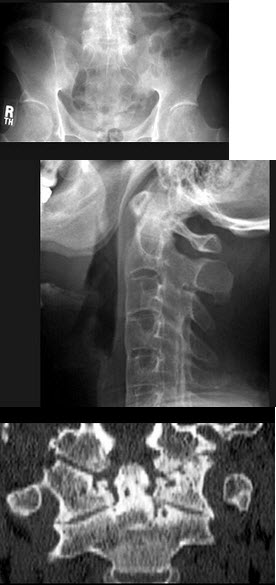

74、单项选择题

男,38岁,慢性颈痛和背痛1年余,结合图像,最可能的诊断是()

A.强直性脊柱炎

B.类风湿关节炎

C.Reiter综合征

D.关节结核

E.痛风